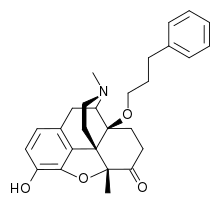

Morphinones and morphols

- 14-Cinnamoyloxycodeinone

- 14-Ethoxymetopon

- 14-Methoxymetopon

- 14-Phenylpropoxymetopon

- 3-Acetyloxymorphone

- 3,14-Diacetyloxymorphone

- 7-Spiroindanyloxymorphone

- 8,14-Dihydroxydihydromorphinone

- Acetylcodone

- Acetylmorphone

- α-hydrocodol (=dihydrocodeine, )

- Benzhydrocodone

- Bromoisopropropyldihydromorphinone cas?

- Codeinone

- Codoxime

- Conorfone (codorphone)

- IBNtxA

- Thebacon (acetyldihydrocodeinone, dihydrocodeinone enol acetate)

- Hydrocodone

- Hydromorphone

- Hydroxycodeine

- Metopon (=methyldihydromorphinone)

- Morphenol

- Morphinone

- Morphol

- N-Phenethyl-14-ethoxymetopon

- Noroxymorphone

- Oxycodone

- Oxymorphol

- Oxymorphone

- Pentamorphone

- Semorphone

Structures

| Morphinones and morphols | ||||

|---|---|---|---|---|

14-Cinnamoyloxycodeinone 14-Cinnamoyloxycodeinone |

14-Ethoxymetopon 14-Ethoxymetopon |

14-Methoxymetopon 14-Methoxymetopon |

14-Phenylpropoxymetopon 14-Phenylpropoxymetopon |

7-Spiroindanyloxymorphone 7-Spiroindanyloxymorphone |

8,14-Dihydroxydihydromorphinone 8,14-Dihydroxydihydromorphinone |

Acetylcodone Acetylcodone |

Acetylmorphone Acetylmorphone |

α-hydrocodol α-hydrocodol(Dihydrocodeine) |

Bromoisopropropyldihydromorphinone Bromoisopropropyldihydromorphinone |

Codeinone Codeinone |

Codorphone Codorphone |

Codol Codol(Codeine Phosphate) |

Codoxime Codoxime |

IBNtxA IBNtxA |

Thebacon Thebacon |

Hydrocodone Hydrocodone |

Hydromorphone Hydromorphone |

Hydroxycodeine Hydroxycodeine |

Metopon Metopon(methyldihydromorphinone) |

Morphenol Morphenol |

Morphinone Morphinone |

Morphol Morphol |

N-Phenethyl-14-ethoxymetopon N-Phenethyl-14-ethoxymetopon |

Oxycodone Oxycodone |

Oxymorphol Oxymorphol |

Oxymorphone Oxymorphone |

Pentamorphone Pentamorphone |

Semorphone Semorphone |